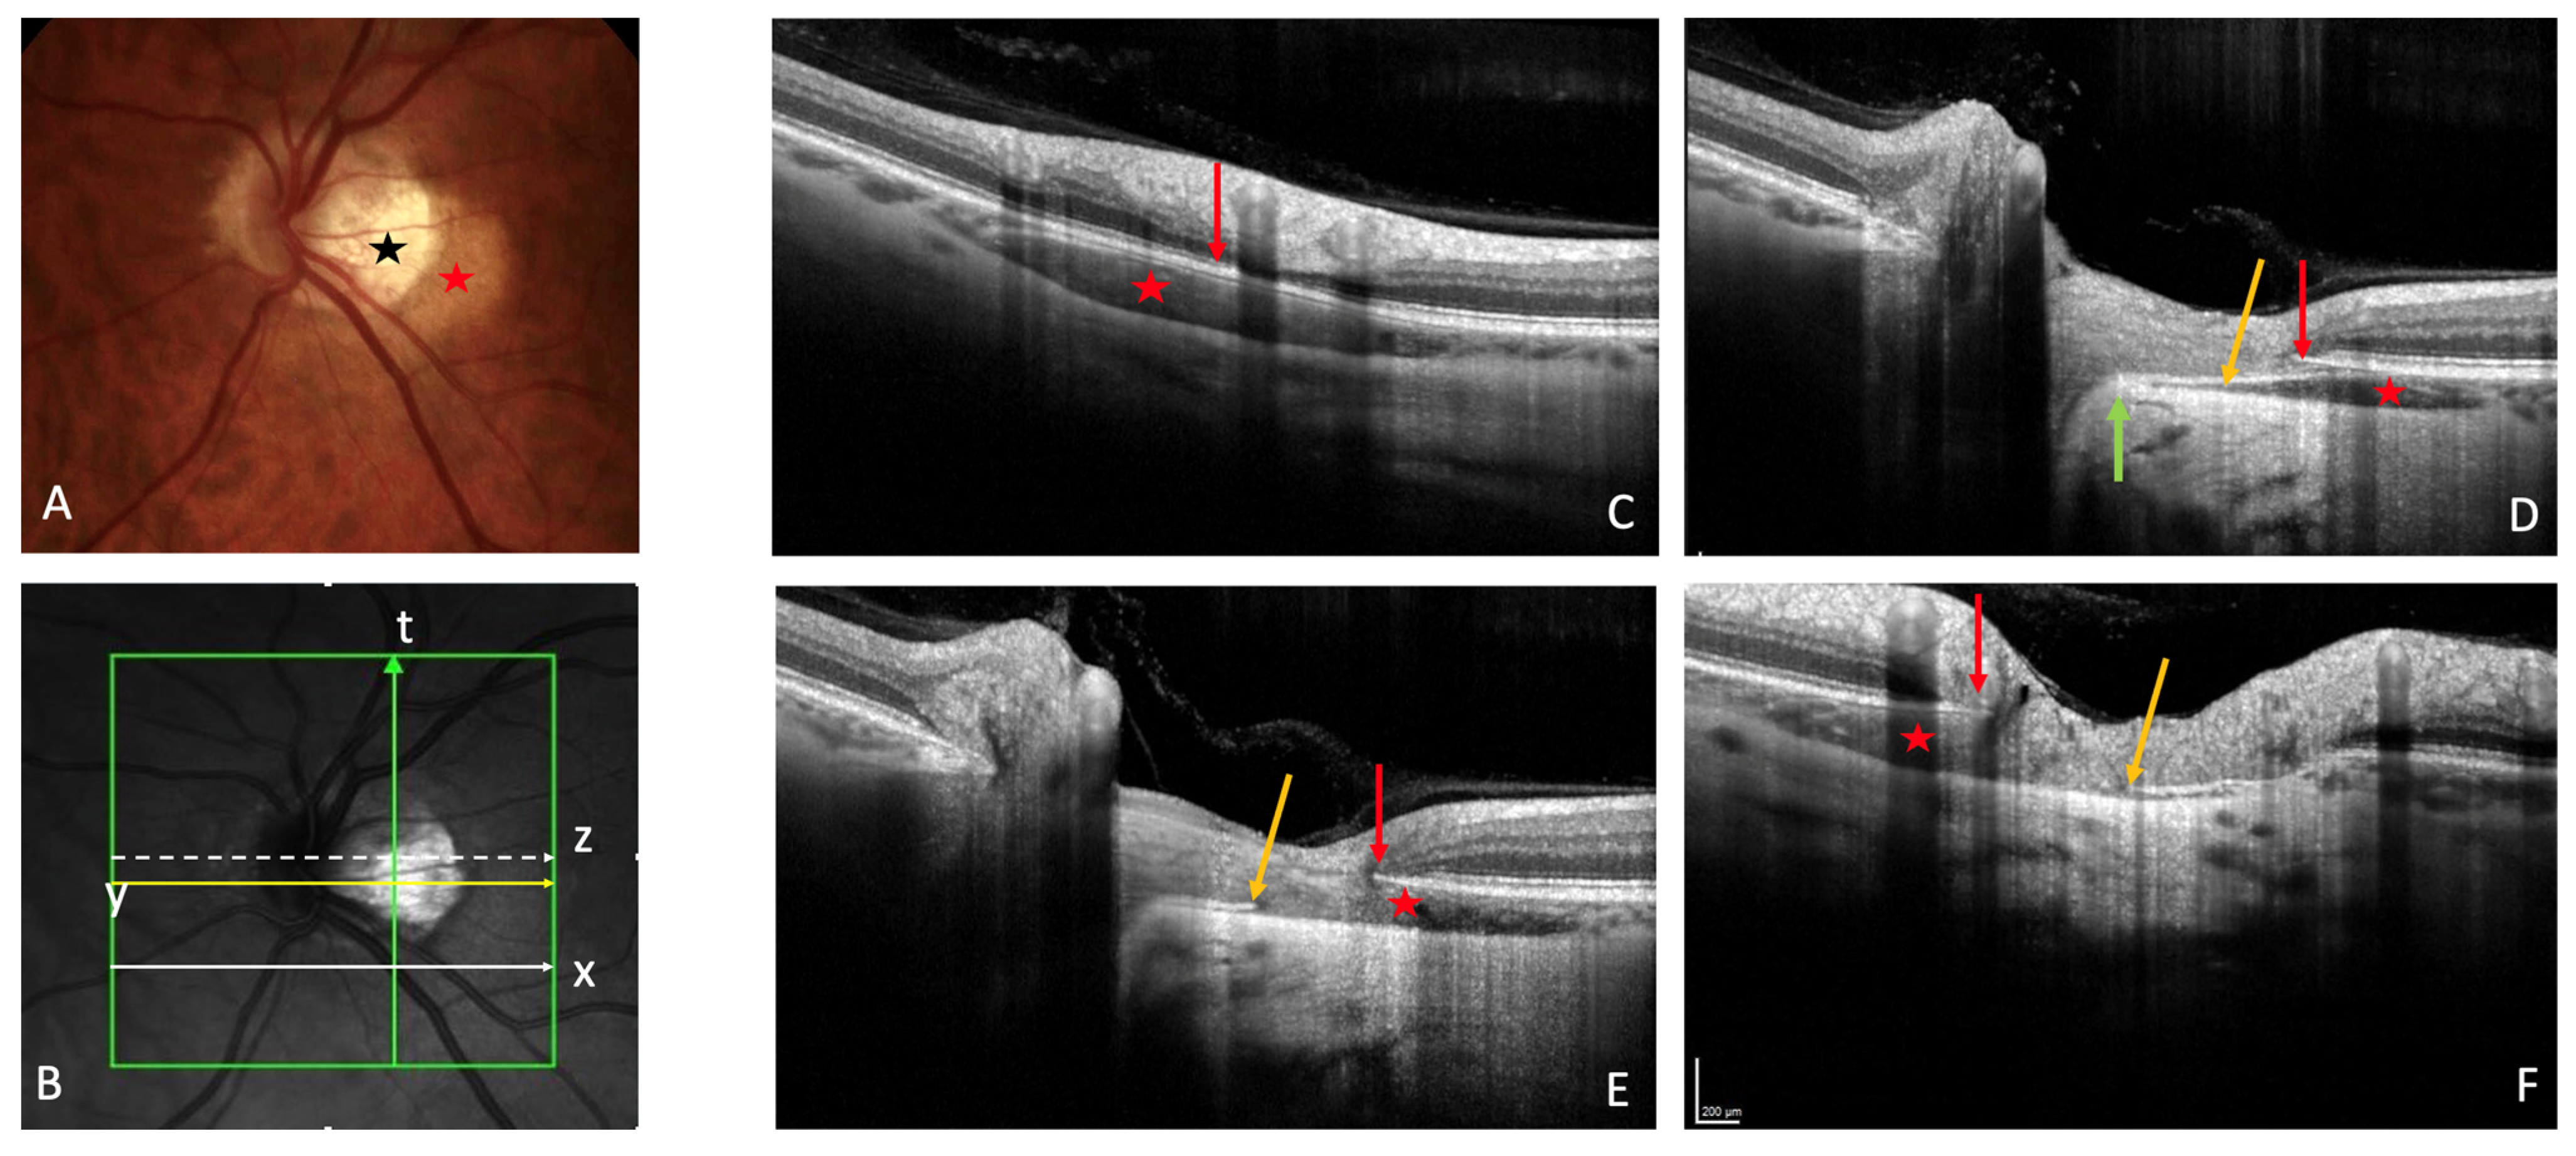

3.1. Fundoscopy and OCT

5. Structural Changes in the Vicinity of the PICC

5.1. Peripapillary Atrophy

5.2. Choroid

5.3. Posterior Scleral Curvature

5.4. Border Tissue of the Choroid

5.5. Vessels